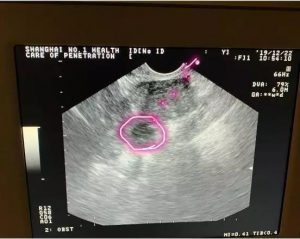

而这种情况,取卵针要经过子宫,长途跋涉后才能刺入卵泡,那肯定疼,我给你取卵也会疼!